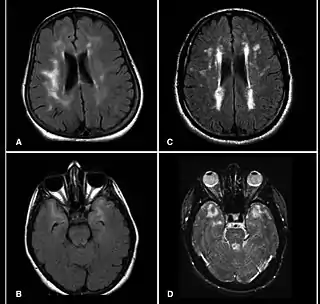

![]() Imagen MRI del cerebro de pacientes con CADASIL mostrando lesiones múltiples | ||

El método preferido de diagnóstico es la resonancia magnética. Las lesiones detectables con este sistema se encuentran concentradas alrededor de los ganglios basales, la sustancia blanca periventricular y el puente de Varolio, y son similares a las que se pueden observar en la enfermedad de Binswanger. Las lesiones en la sustancia blanca suelen estar presentes también en individuos que sufren la mutación del gen en cuestión sin presentar síntomas (Tournier et al, 1993). Otro diagnóstico diferencial a tener en cuenta es la esclerosis múltiple.